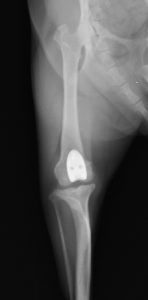

4kg プードル 滑車溝形成術+脛骨粗面移動術。グレード3までは、この手術法で対応可能である

グレード1〜3に対しては下記1&2を組み合わせて整復します。

1 お皿が収まっている滑車溝を深くすること(造溝術)で脱臼を防ぎます。滑車溝の表面の軟骨を保護する方法で行う事で、お皿の滑らかな動きを温存します。(Block Resection 法)

2 膝を曲げの伸ばしする際の筋肉の方向をわずかに矯正すること(脛骨粗面移動術)でお皿がスムーズに動けるようにしてあげます。